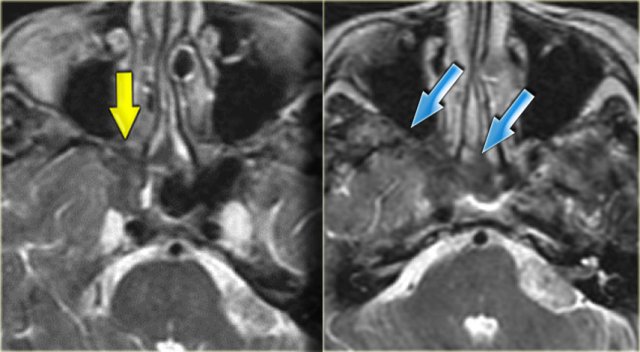

On the left the corresponding MRI.

First study the images, then continue reading.

The findings are:

• Fluid in the right sphenoid sinus (red arrow).

• Hypointense tissue in the left sphenoid sinus (yellow arrows).

• Tracking along the dural margin of the middle cranial fossa (blue arrows).

• Extension into the left zygomatic-masticator space (large yellow arrow).

• Following contrast, there is no solid enhancement of the tissue in the sphenoid space.

Continue with the coronal images.